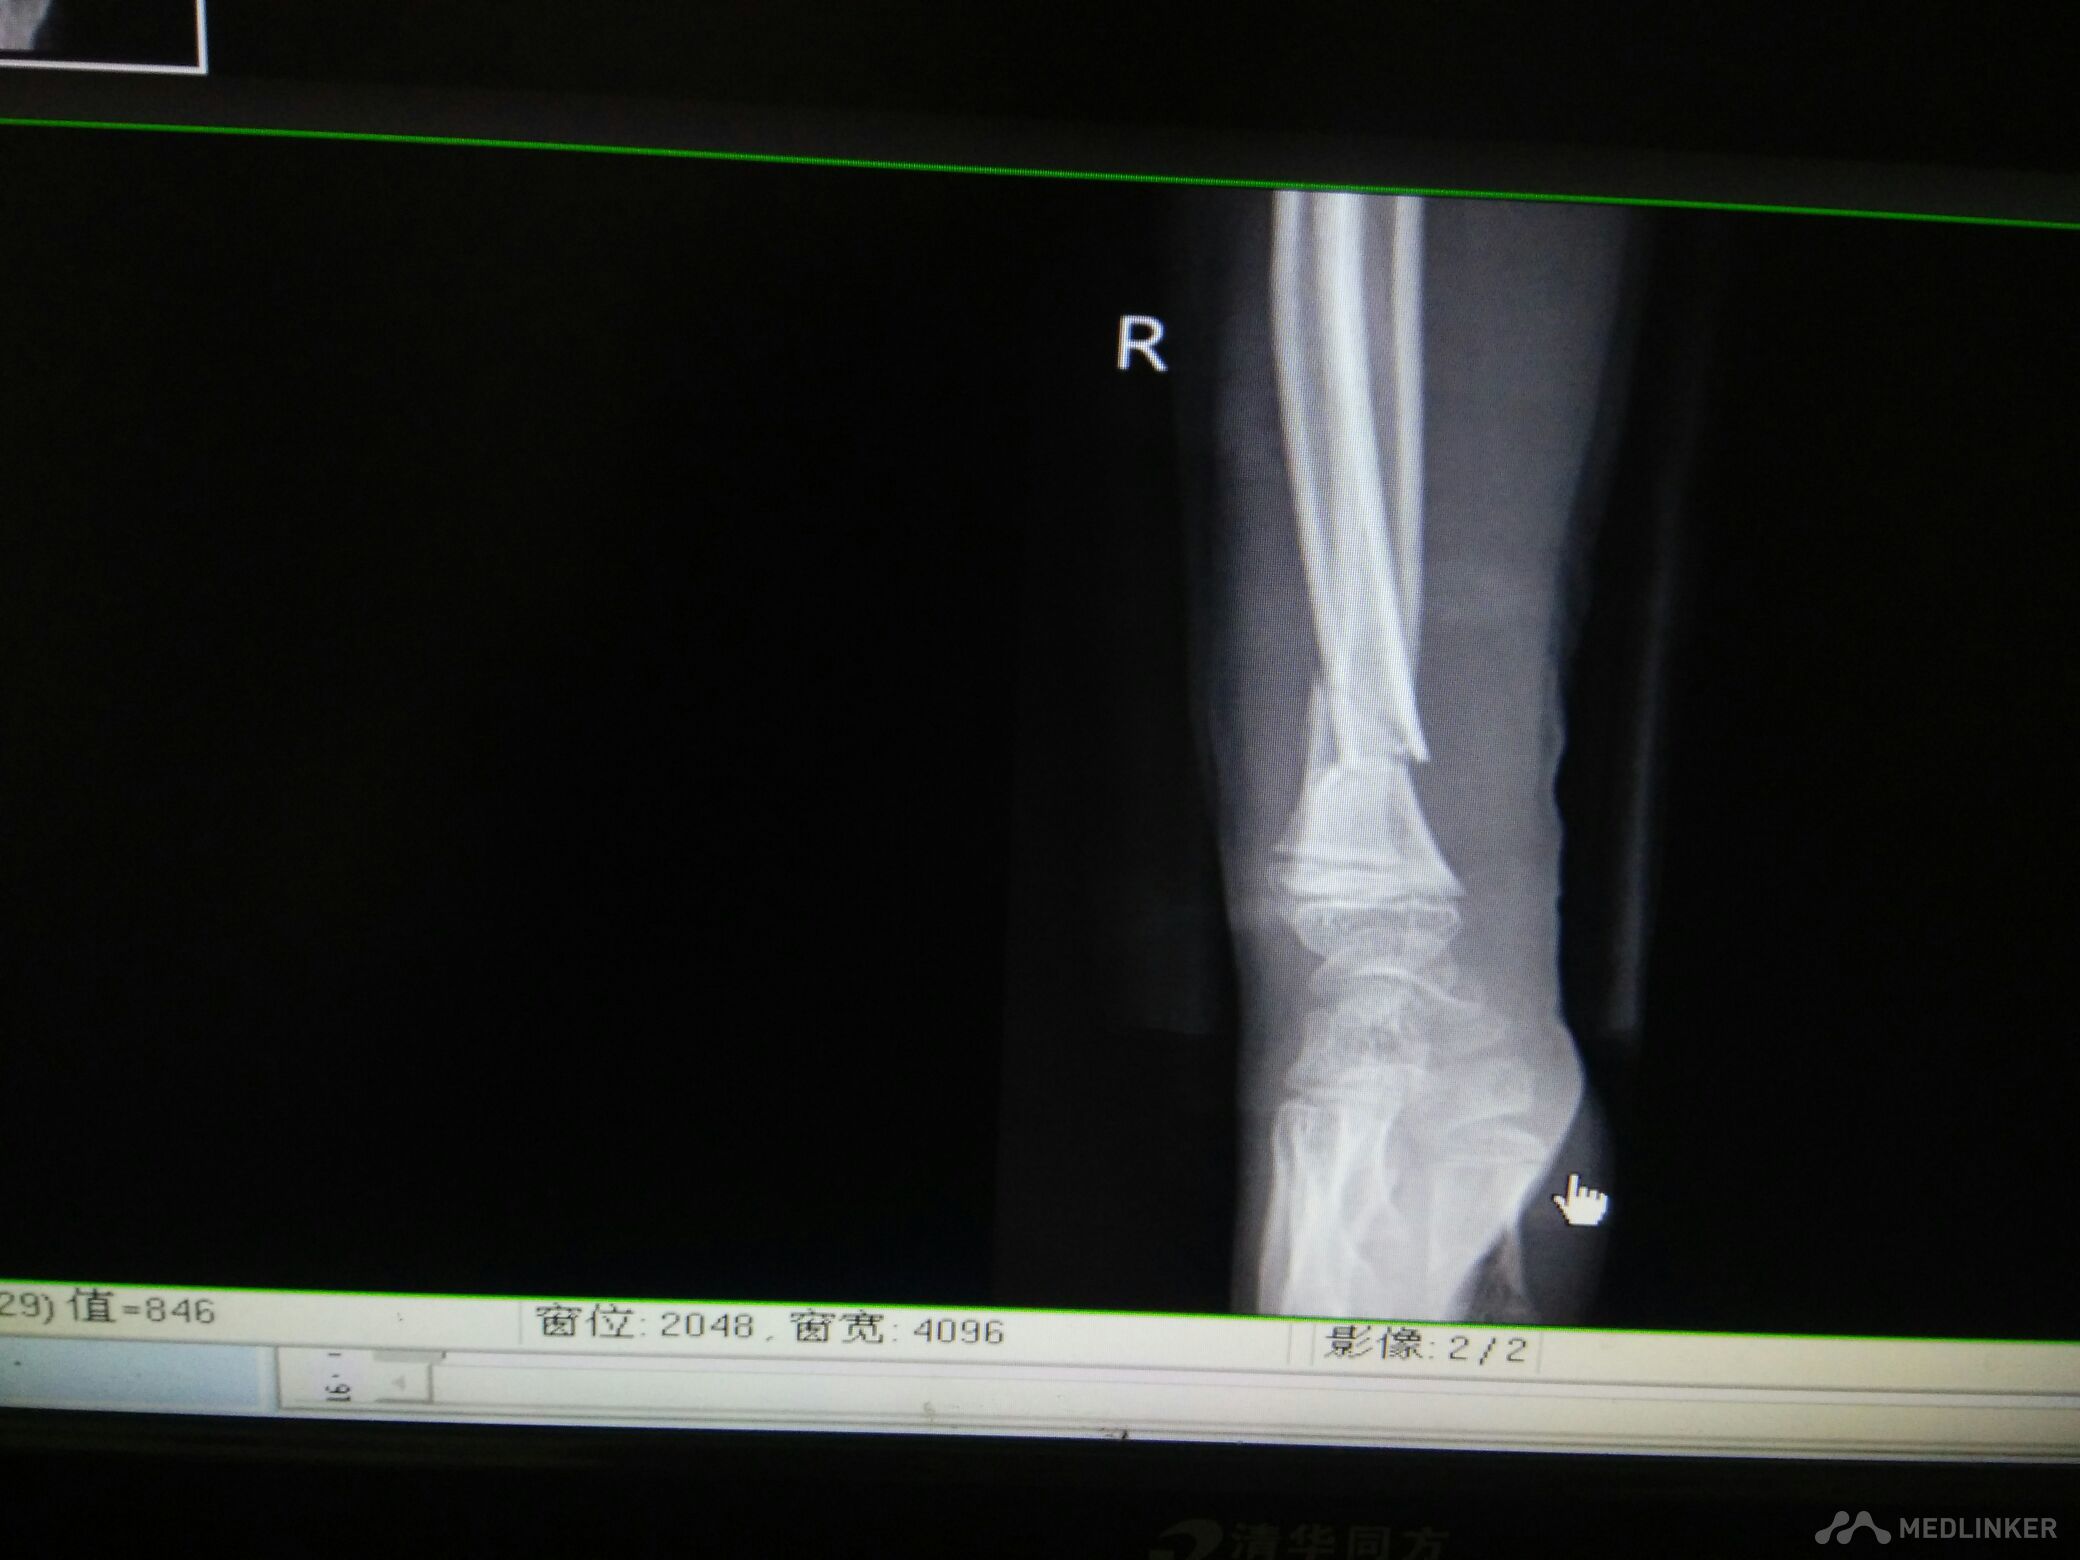

脾破裂,右尺桡骨骨折

尺桡骨骨折

病员男性,15岁。车祸伤致腹痛、右腕部畸形活动受限3小时入院,腹部B超提示:腹腔肠间隙积液,脾破裂。DR检查:右尺桡骨远端骨折。入院后行急诊剖腹探查术脾切除,右尺桡骨手法复位小夹板外固定,右腕复查对位久佳,这种还须手术切开复位吗?